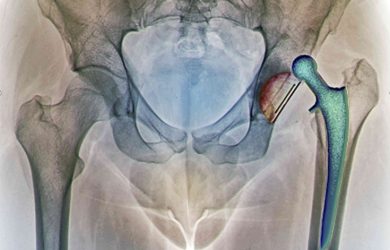

Ендопротезування великих суглобів при пошкодженнях та дегенеративно - дистрофічних захворюваннях

Кожен випадок унікальний та індивідуальний. Але, якщо за результатами обстеження Вам встановили такий діагноз, єдиний спосіб позбутися болю та повернутися до активного способу життя - тотальне ендопротезування враженого суглоба.